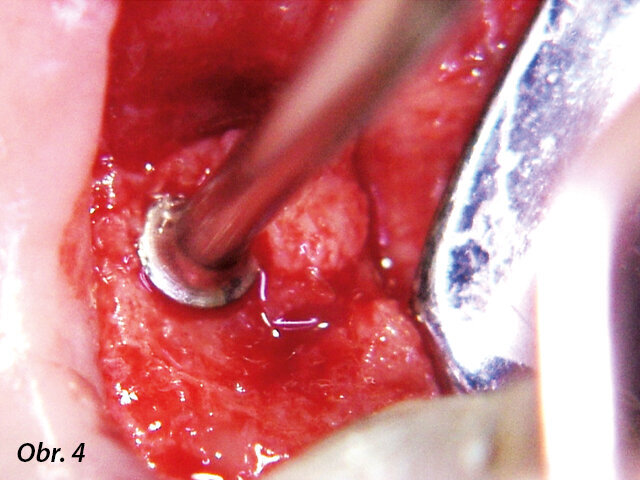

Obrázek 1 zachycuje "split-mouth" případ s oboustranným zákrokem přístrojem INTRALIFT: po oddělení malého krestálního laloku ve tvaru „knížečky“ o rozměru cca 7 × 7 mm bylo dno sinu bezpečně otevřeno pomocí ultrazvukových hrotů Piezotome (obr. 2, 3), membrána sinu oddělená vlivem hydrodynamického kavitačního účinku hrotu Piezotome TKW5 pak byla vtlačena do přístupového kanálu (obr. 4, 5), subantrální konstrukce byla vyplněna 2 cm náhodně přiřazeného biomateriálu a následně byla rána sešita.